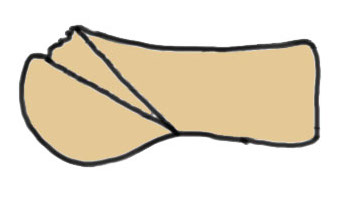

Interposition arthroplasty

Results

Cevik et al Foot Ankle Int 2020

- 24 cases advanced stage Freibergs

- interposition arthroplasty with EDB tendon

- 9 very satisfied, 12 satisfied, 2 moderately satisfied, 1 dissatisfied